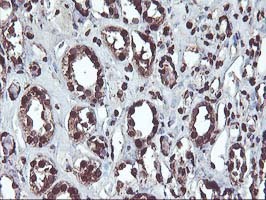

- Immunohistochemical staining of paraffin-embedded Human Kidney tissue within the normal limits using anti-OSGEP mouse monoclonal antibody. (Heat-induced epitope retrieval by 10mM citric buffer, pH6.0, 100C for 10min, TA503002)